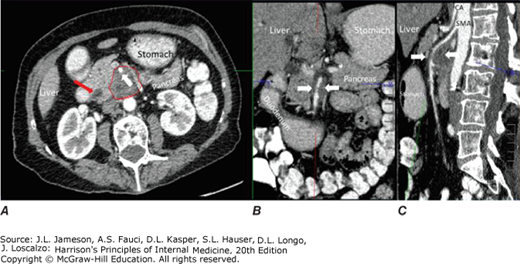

Selected images from contrast-enhanced CT in patients with locally advanced adenocarcinoma of the pancreas. A high-quality contrast-enhanced CT scan (arterial phase in Panels A–C and portal venous phase in Panels D–F) is required for optimal staging of pancreas cancer. Panel A demonstrates the typical features of adenocarcinoma of the pancreas on arterial phase axial CT scans (dotted outline) with tumor encasement of the superior mesenteric artery (white arrow). Note the dilatation of the common bile duct (red arrow). Panels B (magnified coronal) and C (sagittal) show reconstruction of CT images into additional orthogonal planes with exquisite details to confirm the unresectable nature of the tumor due to vascular encasement. Panel Ddemonstrates the typical features of adenocarcinoma of the pancreas on portal venous phase axial CT scans in a different subject. The dotted line outlines a pancreas cancer lesion in the pancreatic head, which is encasing the portal splenic confluence (dotted outline). Panels E (white arrow) and F show the pinched appearance of the portal splenic confluence by tumor abutment and invasion of the superior mesenteric vein (white arrow) on coronal and sagittal views. Note the presence of a stent in the common bile duct (red arrow) to help relieve biliary obstruction caused by the tumor. CA, celiac axis; SMA, superior mesenteric artery.